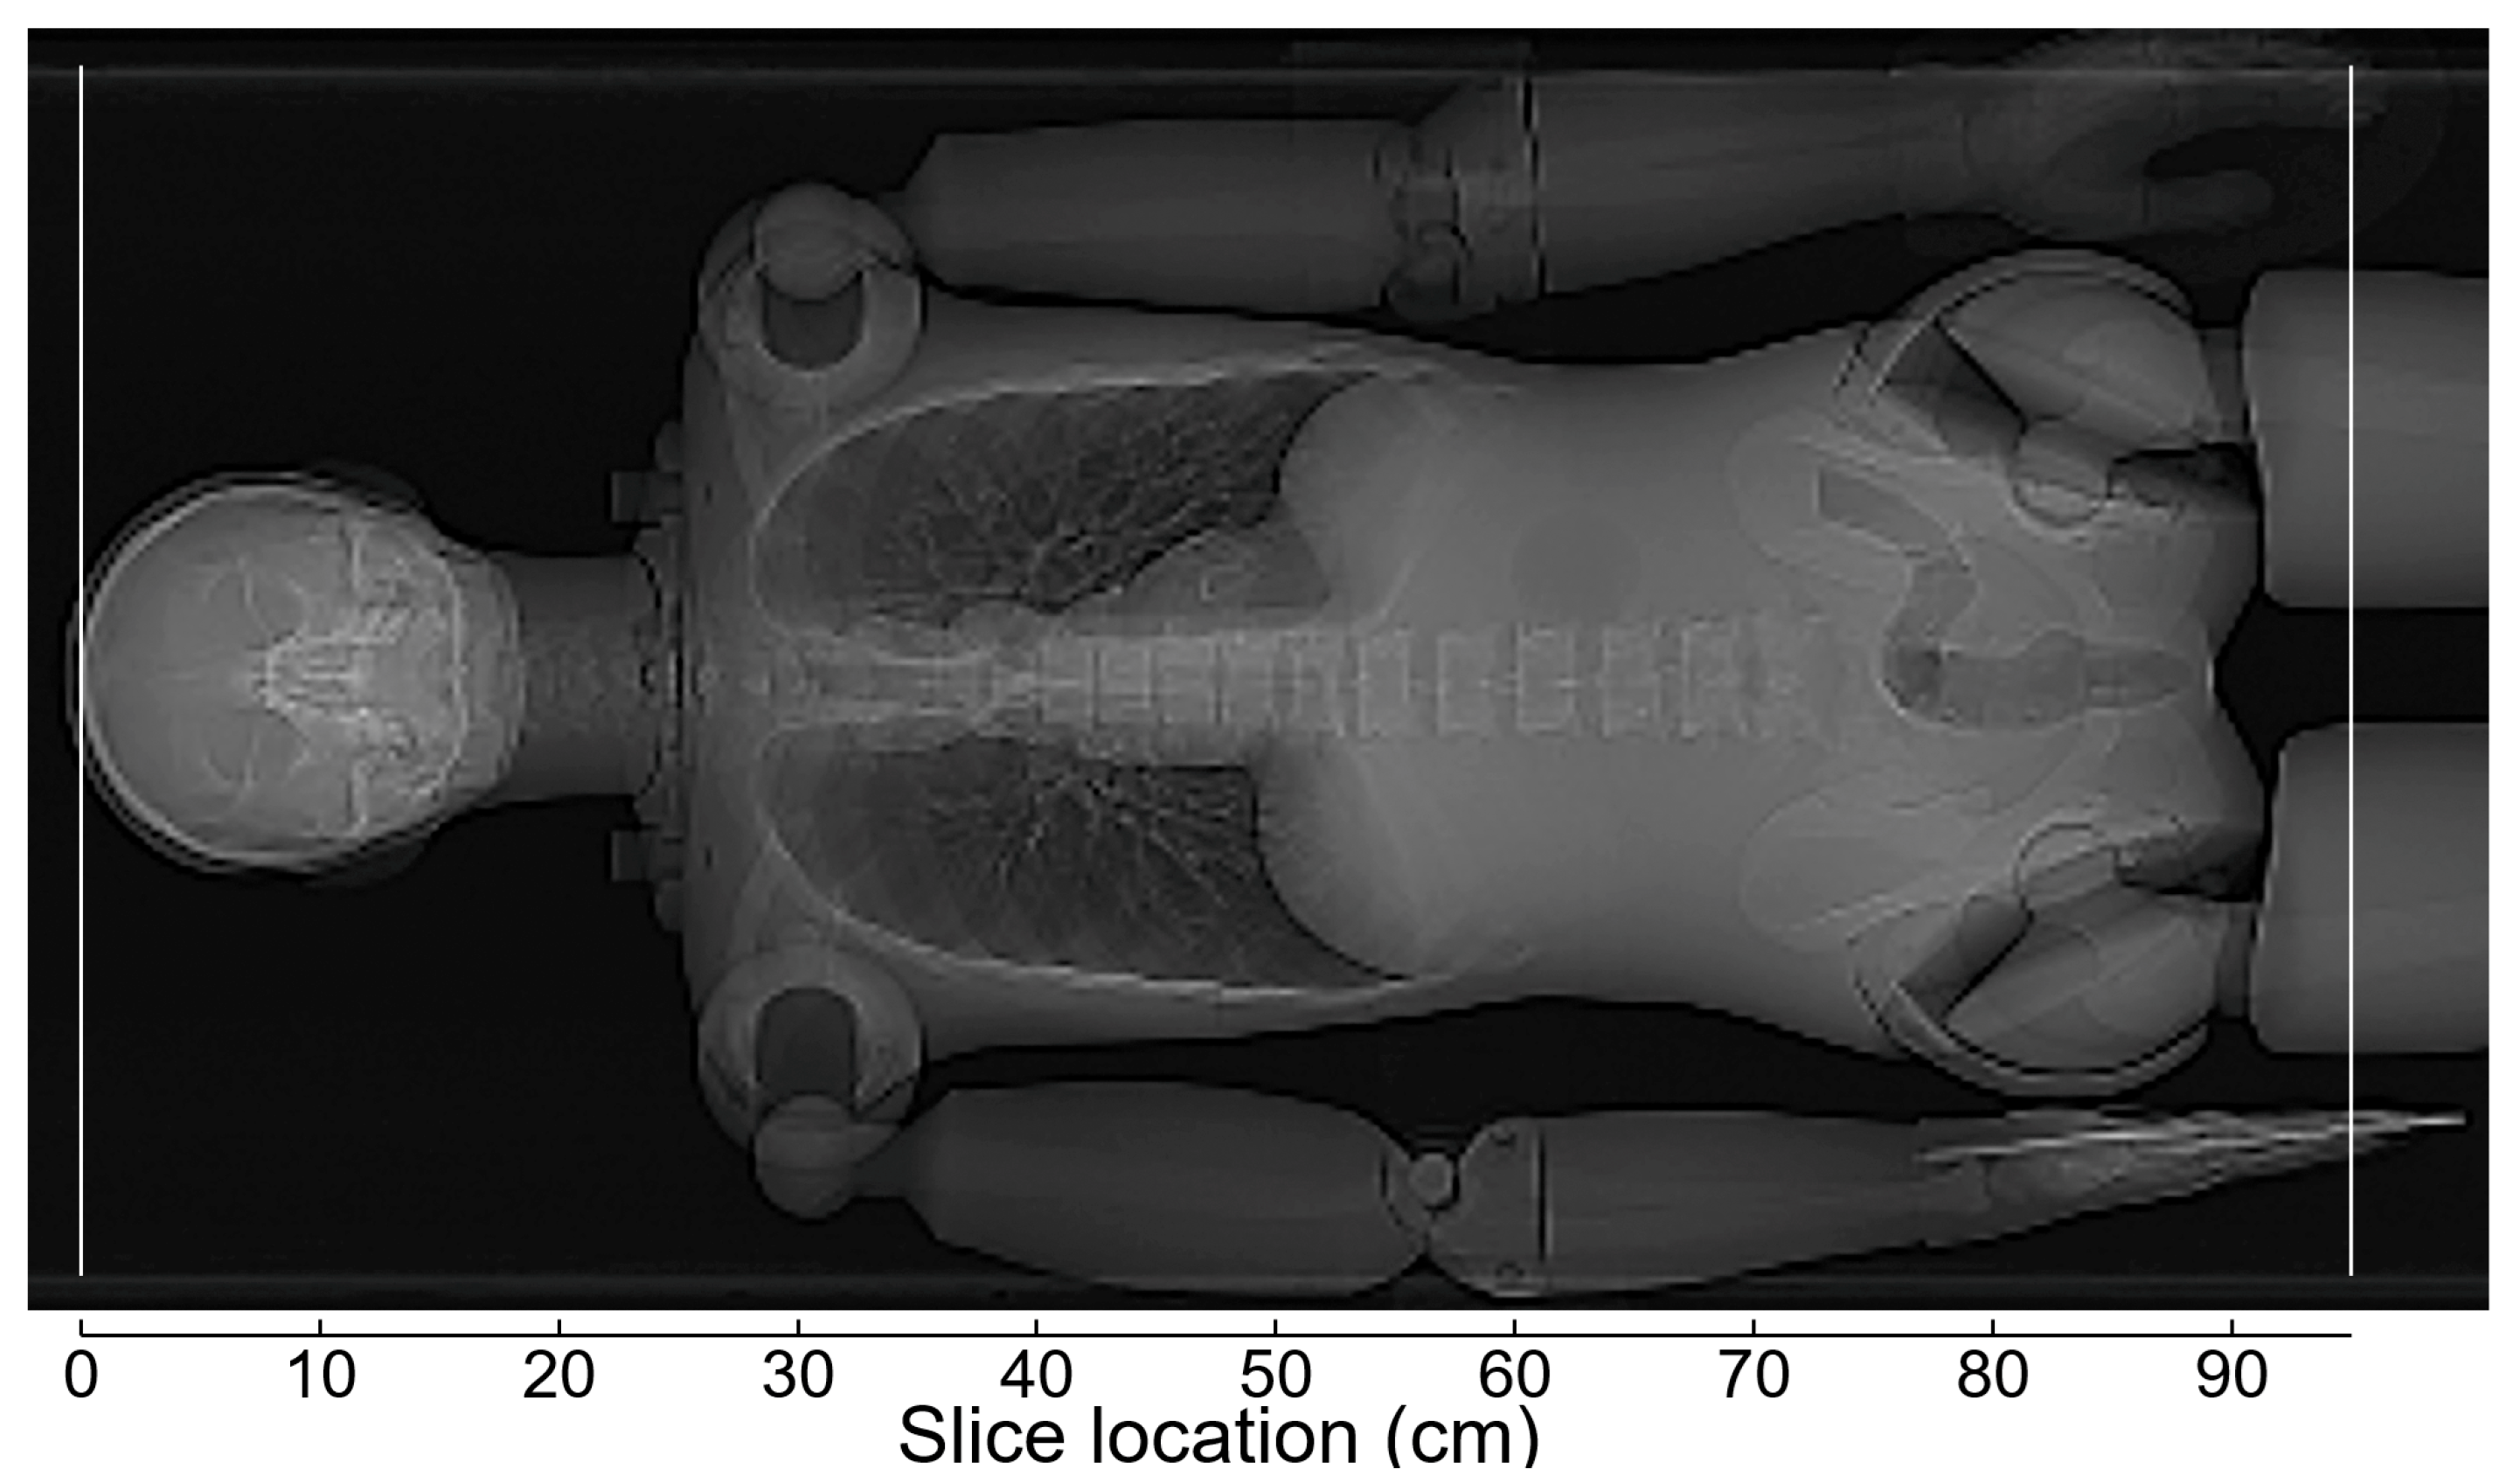

2.3. Effects of Vertical Positioning in Imaging the Anthropomorphic Phantom

2.4. Effects of Scout Imaging Parameters